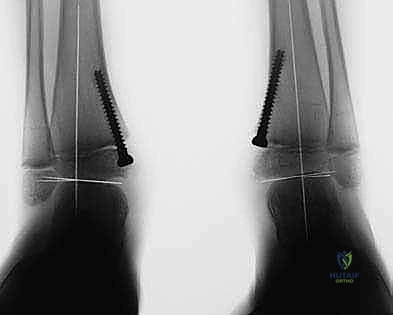

2. التصوير الشعاعي المتقدم:

لا يكتفي الدكتور هطيف بالفحص السريري، بل يتم إجراء صور أشعة سينية (X-rays) للقدم والكاحل أثناء وقوف الطفل (تحمل الوزن). يتم قياس زوايا دقيقة جداً لتقييم مدى الانحراف، مثل زاوية الساق والعقب (Tibiocalcaneal angle) وزوايا المفاصل الأخرى.

الخطوة الرابعة: تثبيت الشريحة (8-Plate)

بمهارة فائقة، يقوم الدكتور هطيف بوضع الشريحة المعدنية المصنوعة من التيتانيوم الطبي النقي فوق مركز النمو. يتم تثبيت الشريحة باستخدام مسمارين صغيرين؛ أحدهما فوق خط النمو والآخر تحته. هذه المسامير لا تخترق مركز النمو نفسه، مما يضمن عدم تدميره.